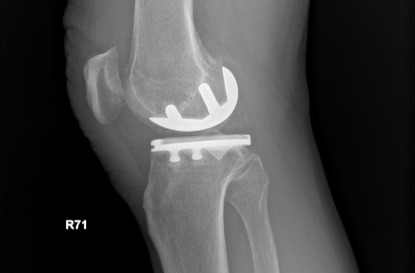

半膝人工關節置換術術後X光(膝蓋側面)